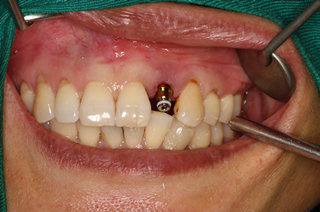

种植体完成后

种牙完成后的邓女士

经过麦芽口腔医师团队的努力,邓女士终于露出了久违的笑容。邓女士表示:“医生的技术很好,整个过程丝毫没有感觉到是在做一个手术,感觉就是在牙椅上躺了一个小时,醒来之后牙齿残根不见了,种植牙和我的真牙丝毫看不出有什么区别,感谢麦芽口腔”。

种牙后的牙齿情况